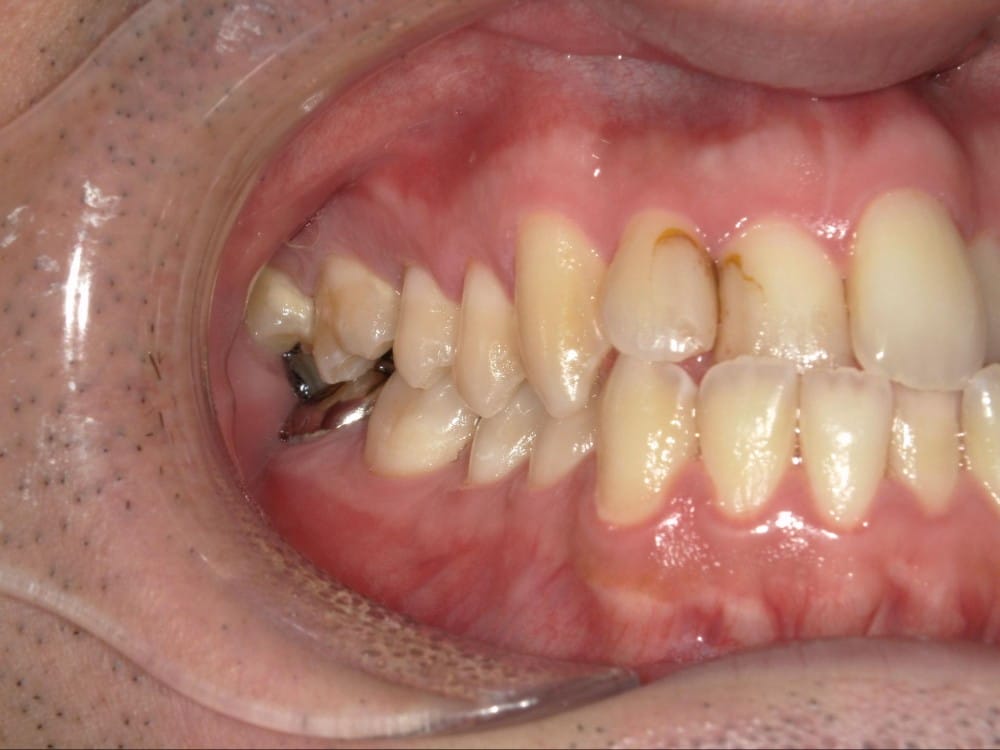

このような奥歯の移動量が大きい症例では、マウスピースだけでは難しいことがあり、カリエールとよばれる装置を補助的に使用し、上下の噛み合わせの前後関係を整えることで、手術を行わずに機能面と見た目の両方が改善することがあります。

一時的に前歯は噛み合わせが開いていますが、受け口の矯正では、最終段階で前歯ばっかりあたって奥歯がしっかり噛まないということも起こりやすいので、あえて狙って動かしています。

ここから上下透明なマウスピースに変え、仕上げていきました。